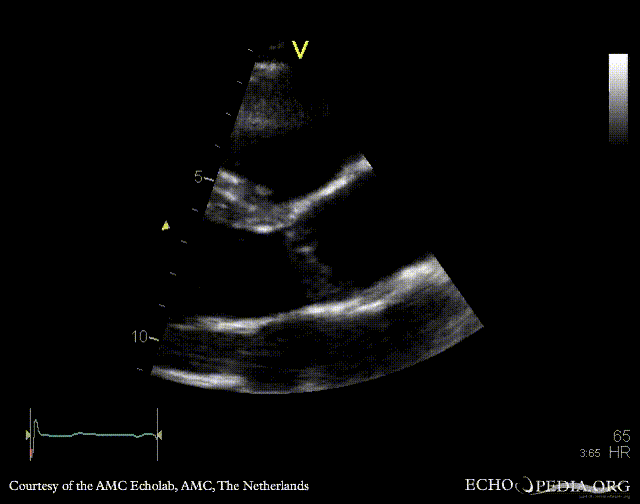

E00341.gif E00342.gif

A5CH: Color Doppler, moderate aortic regurgitation PSAX: bicuspid aortic valve